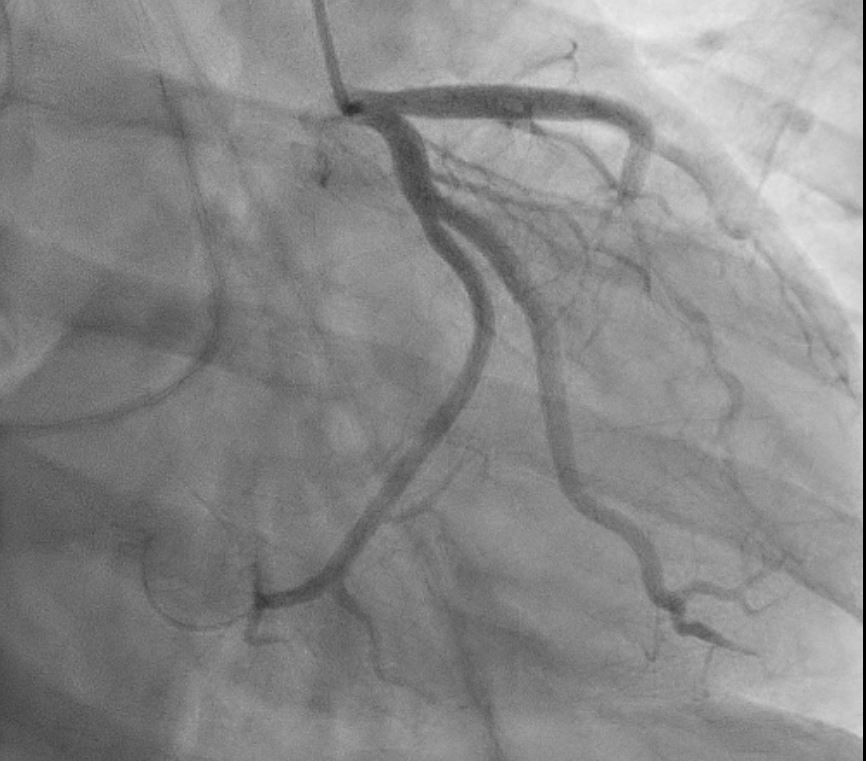

Proceeded with Primary PCI that revealed normal coronaries with mid LAD myocardial bridging . ST elevation resolved in cath lab.